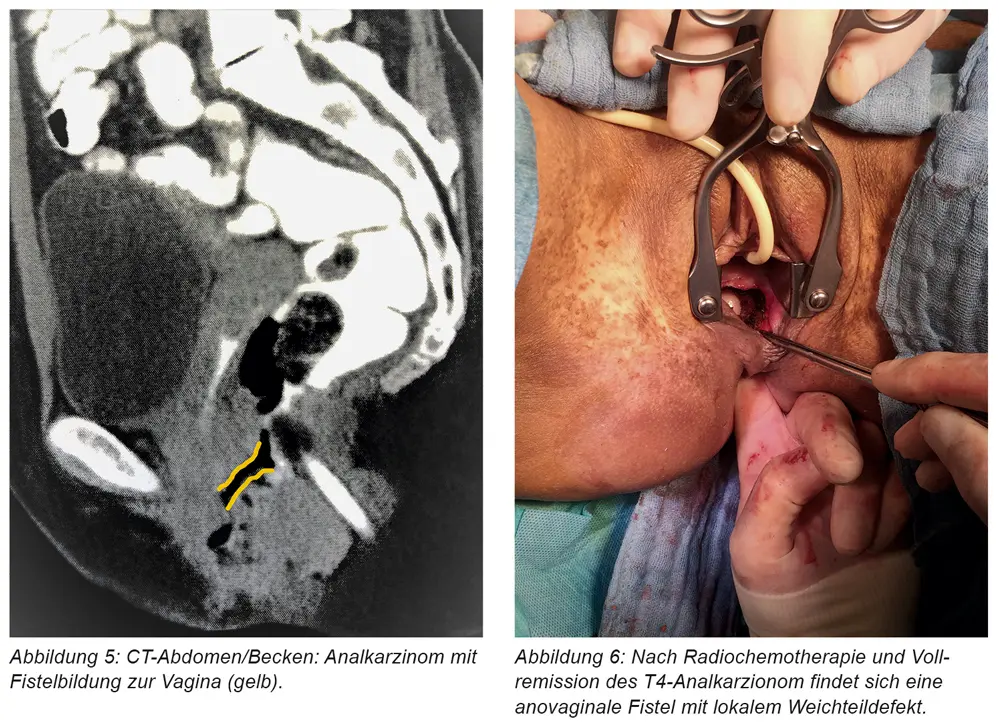

Die Diagnose einer Fistel Schwangerschaft erfolgt in der Regel durch eine Kombination aus Anamnese, körperlicher Untersuchung und bildgebenden Verfahren. Die Anamnese umfasst Fragen zu den Symptomen, der Krankengeschichte und der Schwangerschaftsgeschichte. Die körperliche Untersuchung umfasst die Untersuchung der Vagina, des Rektums und des Beckens. Bildgebende Verfahren, wie z. B. Eine Ultraschalluntersuchung, eine Magnetresonanztomographie (MRT) oder eine Computertomographie (CT), können helfen, die Fistel zu lokalisieren und ihren Verlauf zu bestimmen.